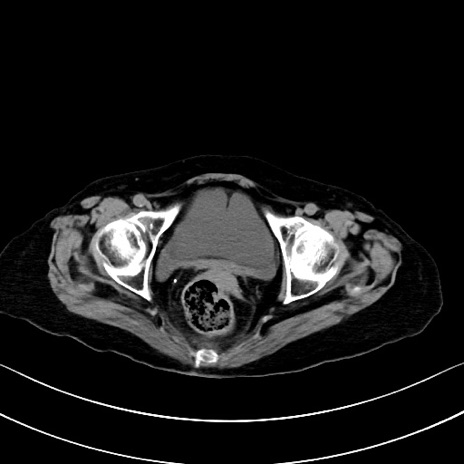

横断像

他院CT